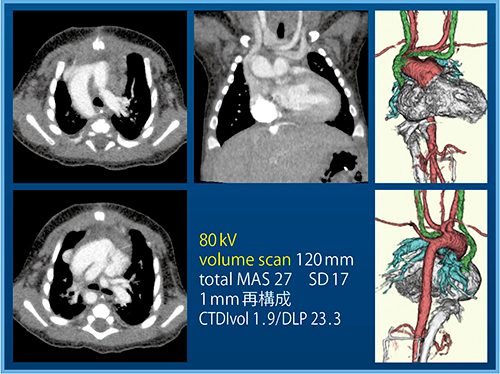

症例3は,3か月,男児,総動脈幹症を含む複雑心奇形症例である。新生児/乳児の心大血管の撮影は難しいが,当センターでは造影剤量(300mg/mL)1.5mL/kgを生理的食塩水にて2:1で混和し,計15mLを20mLシリンジに入れて使用換算量を設定している。低管電圧(80kV)のボリュームスキャンを行うことで,わずかな線量でも心電図同期をかけることなく,十分な画像が得られている(図6)。

図6 症例3:総動脈幹症を含む複雑心奇形症例(3か月,男児)